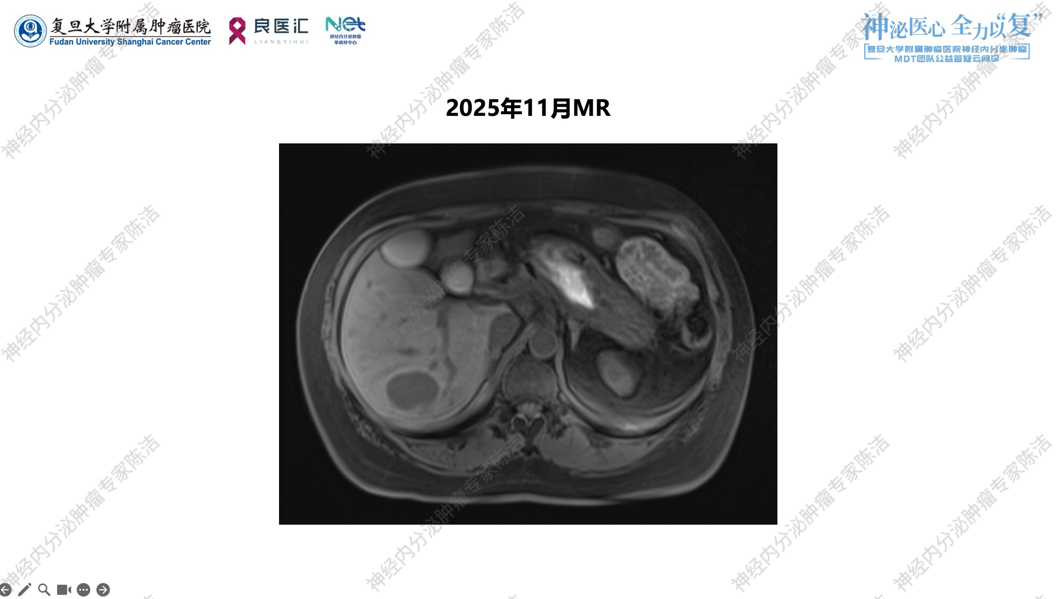

术后长效奥曲肽30mg q4w治疗,期间定期复查。至2025年6月,CT及MR图像均显示肝内散在的转移灶较2024年3月及2023年9月明显增多、增大,且血供丰富,属于明确的影像学PD状态。2025年11月MR评估,估计肝肿瘤负荷在20%—30%左右。

2025年11月为筛选临床试验进行的68Ga-DOTATATE PET/CT显示,原发灶切除后无复发迹象,但肝内转移灶较基线明显进展,且均为SSTR高表达的弥漫性改变。此外,本次PET/CT意外发现左侧桥小脑角区有一局灶性SSTR摄取增高结节,CT对应区域显示较模糊,结合该部位及显像特点,首先考虑脑膜瘤可能,建议MRI进一步核实,转移瘤可能性较小。